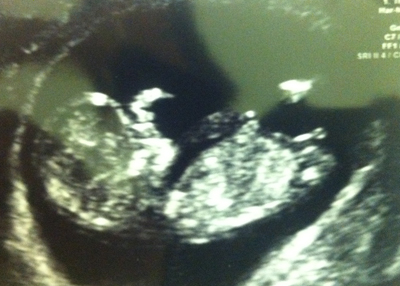

hey! this is an 11w 3d scan-- any ideas?

It looks girly at the moment but being in the 11th week there is still a 50/50 chance it may rise.